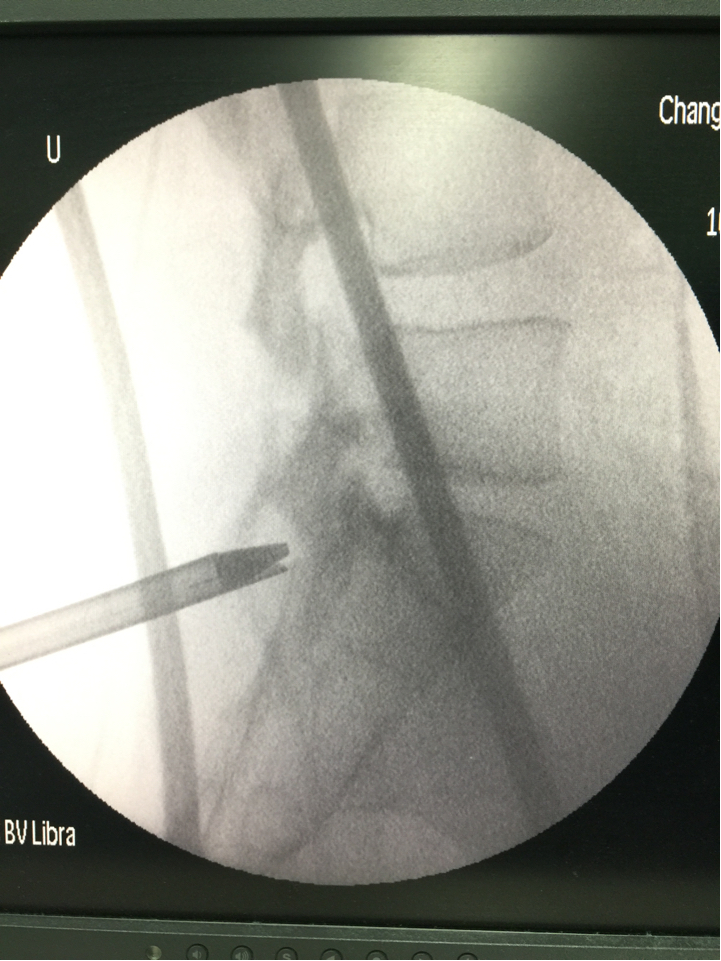

之前介绍的腰椎内镜技术是经椎间孔入路,也就是从侧门放置内镜工作通道进入椎管。而如果从后门放置通道进入椎管,则是经椎板间隙入路。由于最下面的腰5骶1椎板间隙是最大的,所以经椎板间隙入路最常用于腰5骶1节段。

与椎间孔入路相比,椎板间入路的优势是不需要磨除关节突骨质,术中透视次数更少。